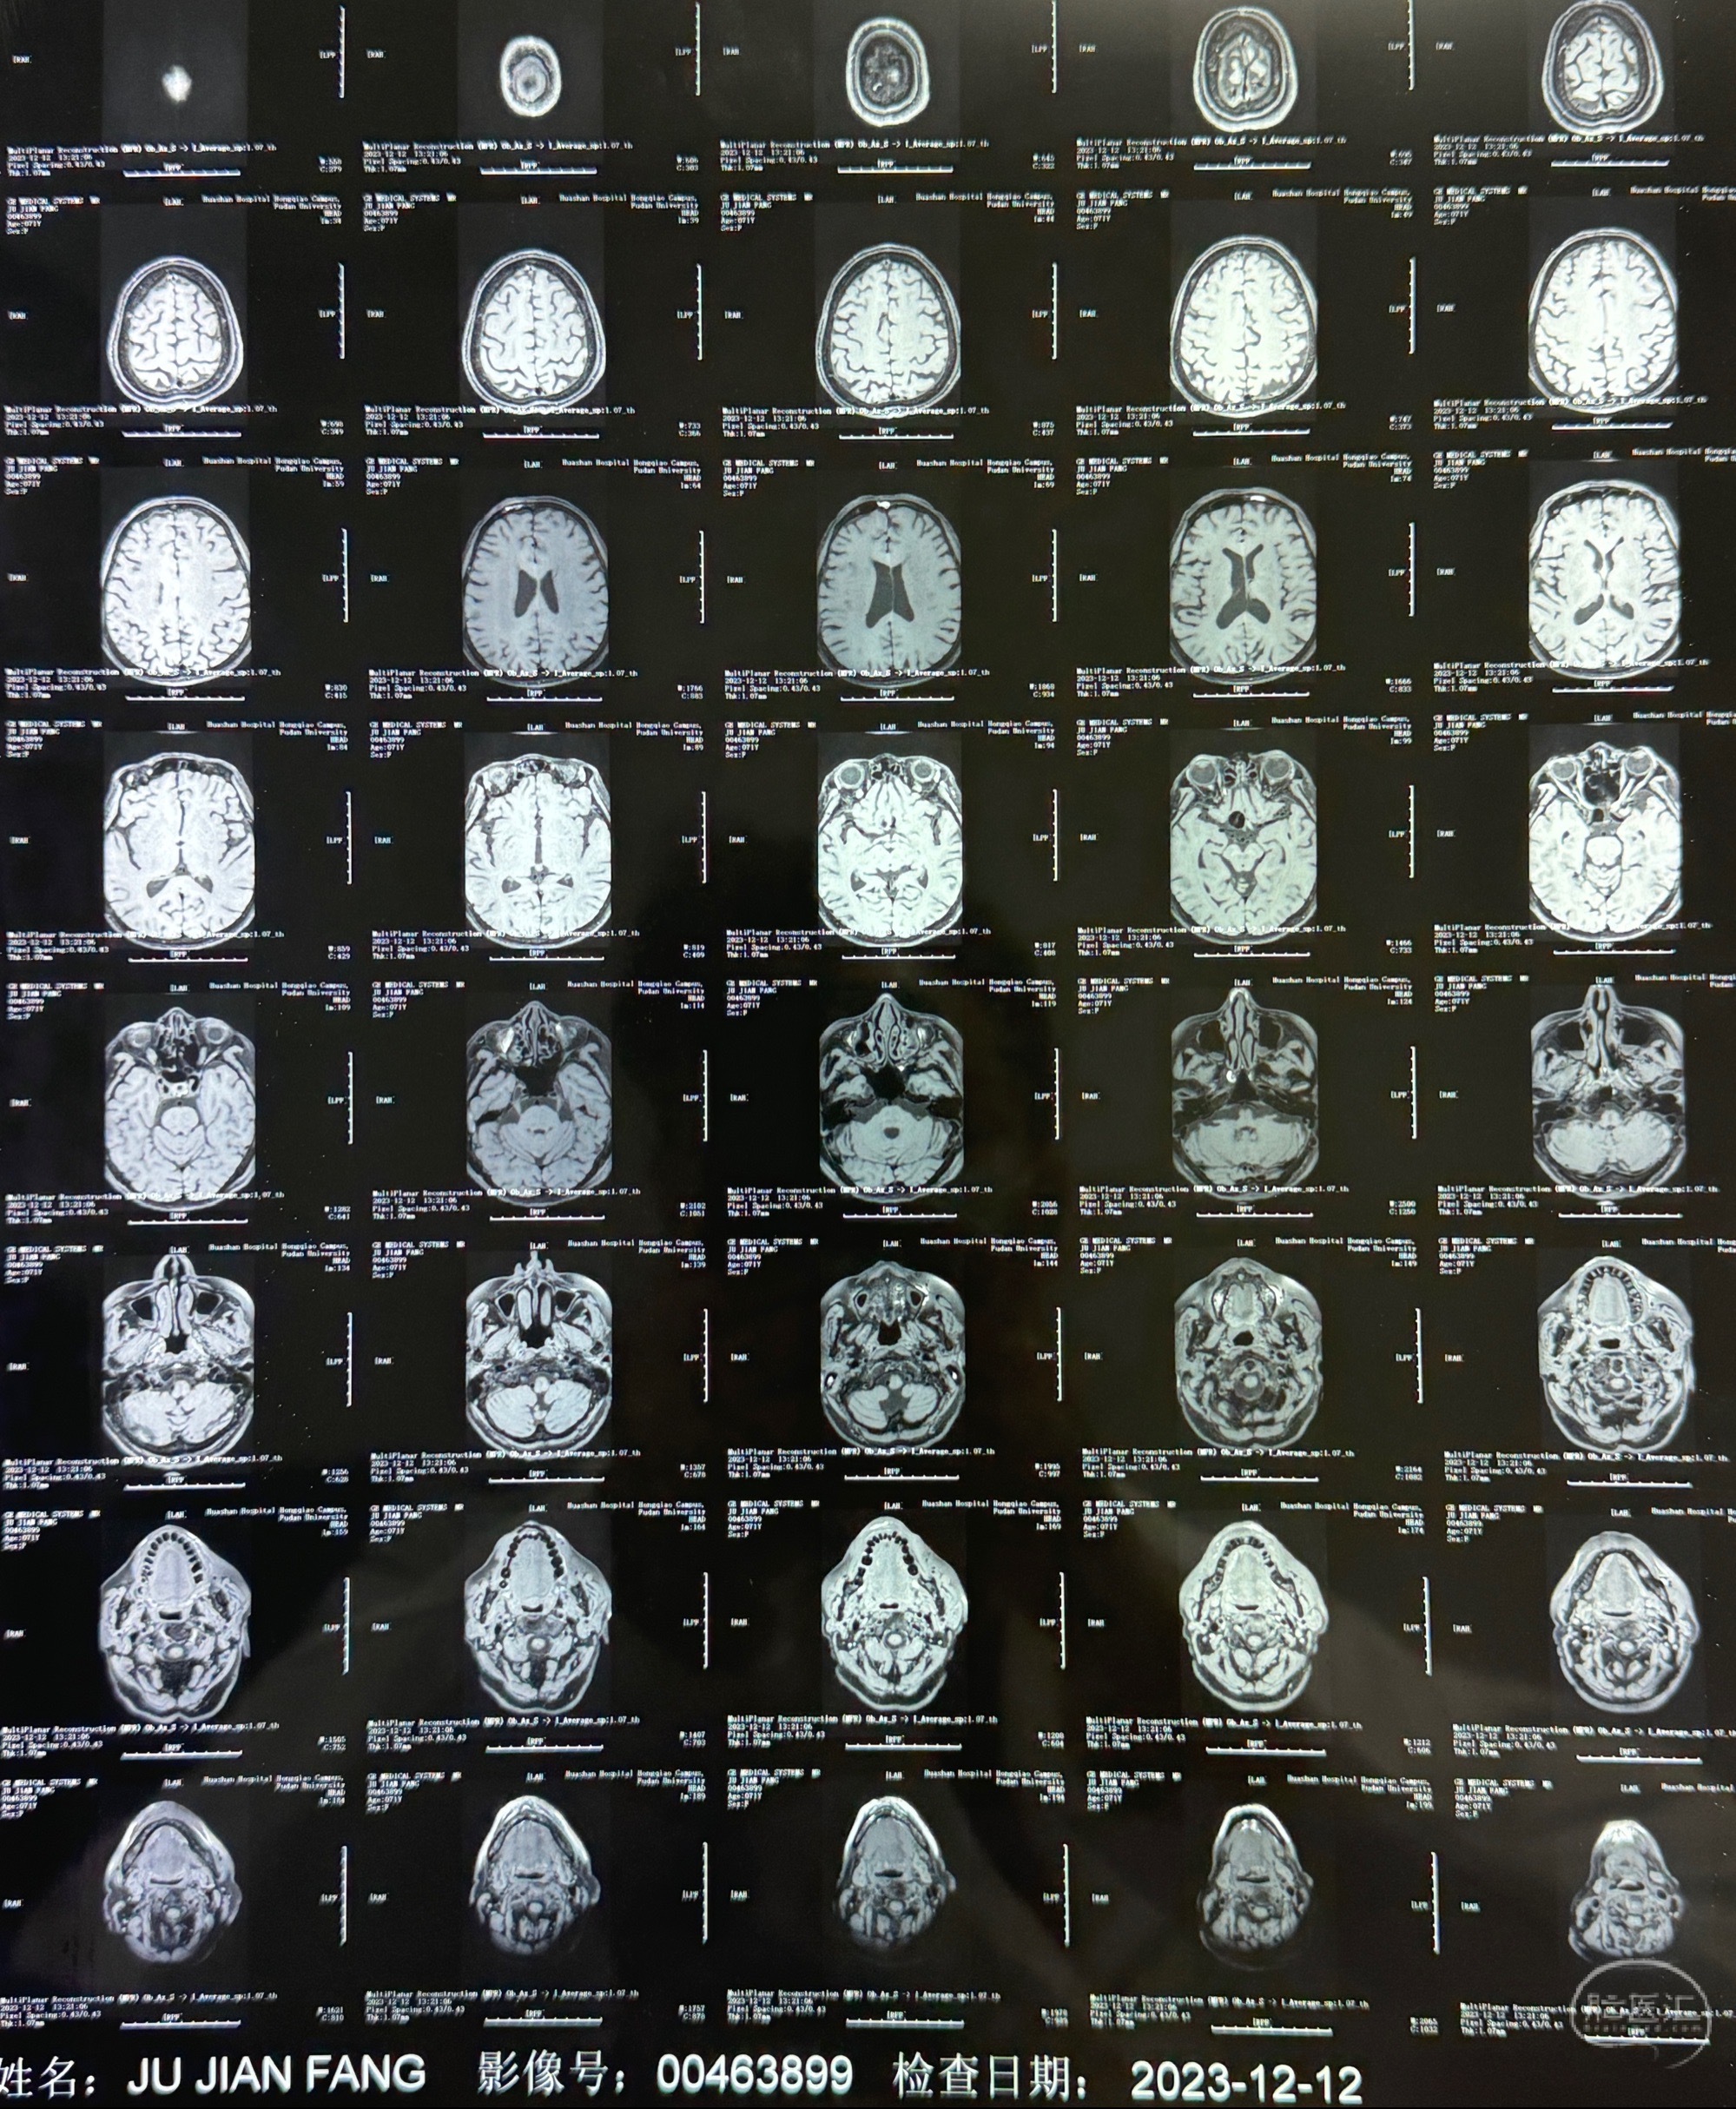

2023-12-12MRI

辅助检查;2023-11 外院 头颅MRI+MRA:左侧颈内动脉C6段动脉瘤;

2023-12-08 复旦大学附属华山医院 全脑血管造影:右侧颈内动脉C6段动脉瘤,瘤颈6.68mm,动脉瘤大小13.28*12.34mm